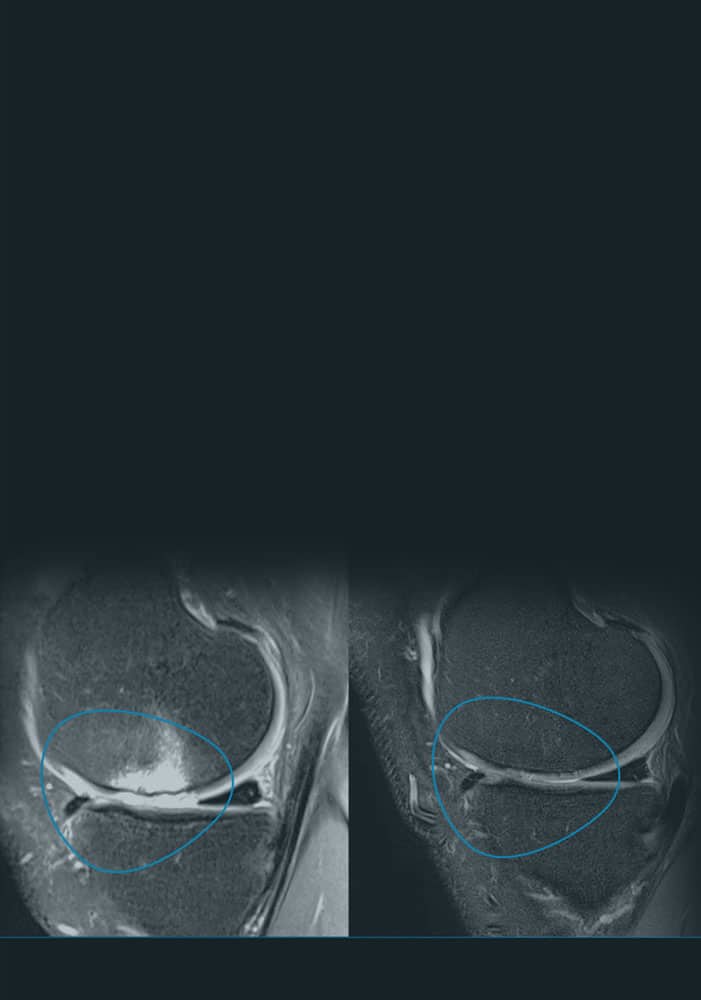

En ITRT hemos demostrado la viabilidad y seguridad de nuestras terapias mediante ensayos clínicos regulados y autorizados por la AEMPS (Agencia Española de Medicamentos y Productos Sanitarios). Una vez superado el ensayo clínico, la AEMPS autoriza el uso del medicamento en pacientes concretos, lo que permite ofrecer tratamientos personalizados con eficacia clínica y capacidad regenerativa demostrada.